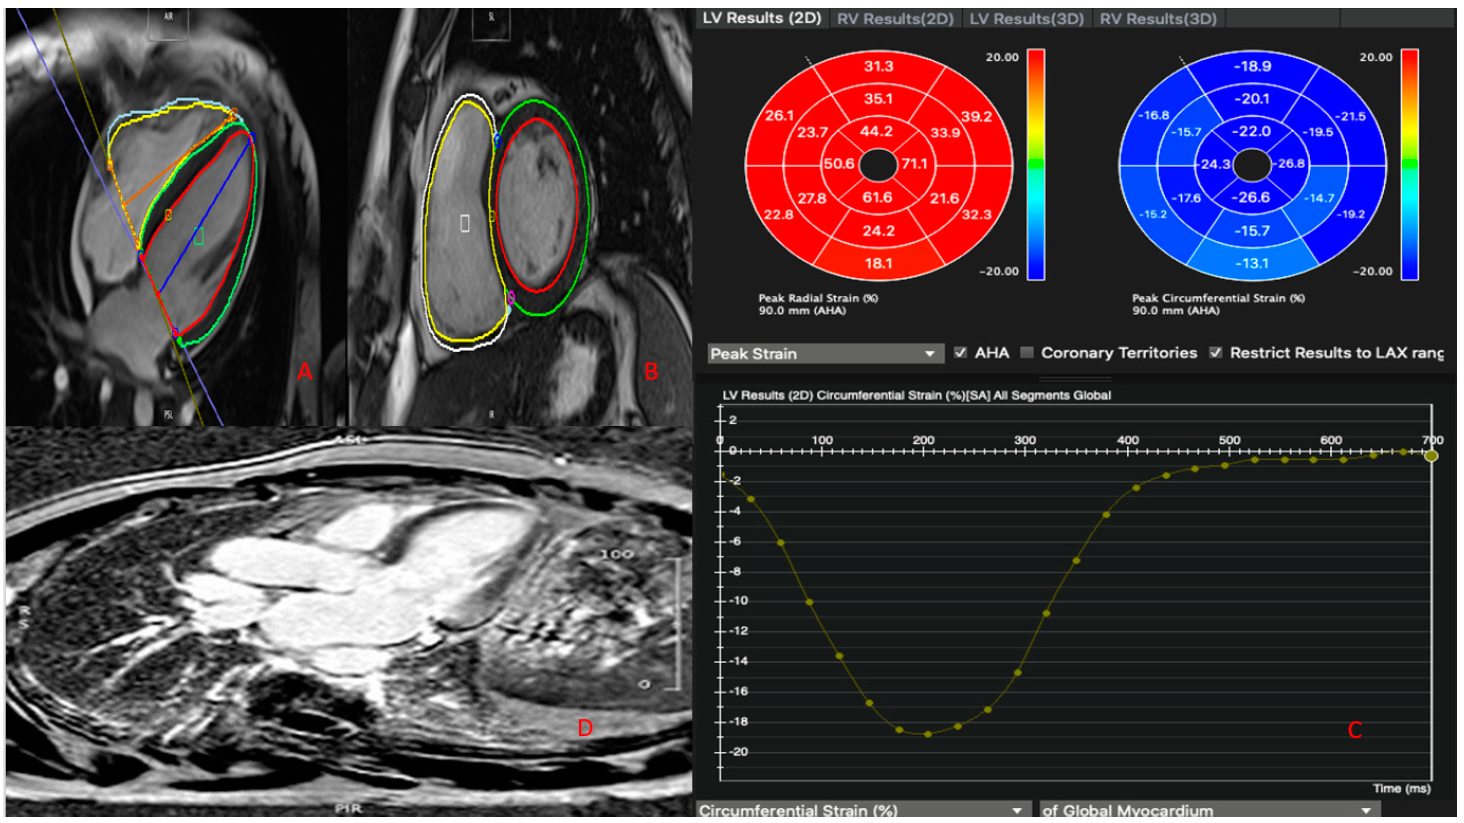

| EDVi LV (mL/mq) | 87.00 ± 13.05 | 81.69 ± 20.16 | 77.75 ± 11.56 | 83.69 ± 16.09 | 0.410 | 0.216 | 0.718 |

| ESVi LV (mL/mq) | 36.53 ± 8.23 | 34.77 ± 12.59 | 37.00 ± 11.74 | 35.88 ± 10.30 | 0.660 | 0.927 | 0.758 |

| LV ejection fraction (%) | 58.13 ± 6.12 | 57.92 ± 6.87 | 53.50 ± 10.63 | 57.47 ± 6.96 | 0.933 | 0.264 | 0.335 |

| LV mass (g/mq) | 64.27 ± 15.40 | 60.92 ± 14.99 | 58.75 ± 8.96 | 62.22 ± 14.36 | 0.567 | 0.507 | 0.790 |

| LV regional wall motion | 4 (26.7%) | 4 (28.6%) | 9 (100%) | 17 (44.7%) | 0.910 | 0.0006 | 0.0010 |

| EDVi RV (mL/mq) | 88.13 ± 16.27 | 80.15 ± 20.05 | 69.50 ± 6.03 | 82.56 ± 17.83 | 0.255 | 0.003 | 0.320 |

| ESVi RV (mL/mq) | 38.13 ± 11.09 | 33.85 ± 10.76 | 28.50 ± 3.70 | 35.19 ± 10.61 | 0.310 | 0.111 | 0.354 |

| RV ejection fraction (%) | 57.33 ± 6.97 | 58.00 ± 6.03 | 58.75 ± 8.18 | 57.78 ± 6.53 | 0.790 | 0.731 | 0.843 |

| RV regional wall motion | 1 (6.7%) | 0 (0.0%) | 0 (0.0%) | 1 (2.6%) | 0.558 | 0.558 | 1.000 |

| Tissue Characterization | |||||||

| LV edema | 9 (60.0%) | 7 (50.0%) | 6 (66.7%) | 22 (57.9%) | 0.754 | 0.605 | 0.484 |

| LV LGE | 13 (86.7%) | 11 (78.57%) | 3 (33.3%) | 27 (71%) | 0.164 | 0.0085 | 0.0005 |

| LGE LV ischemic pattern | 0 (0.0%) | 11 (78.57%) | 0 (0.0%) | 11 (29%) | <0.0001 | 0 | <0.0001 |

| RV edema | 0 (0.0%) | 0 (0.0%) | 0 (0.0%) | 0 (0.0%) | 0 | 0 | 0 |

| RV LGE | 0 (0.0%) | 0 (0.0%) | 0 (0.0%) | 0 (0.0%) | 0 | 0 | 0 |